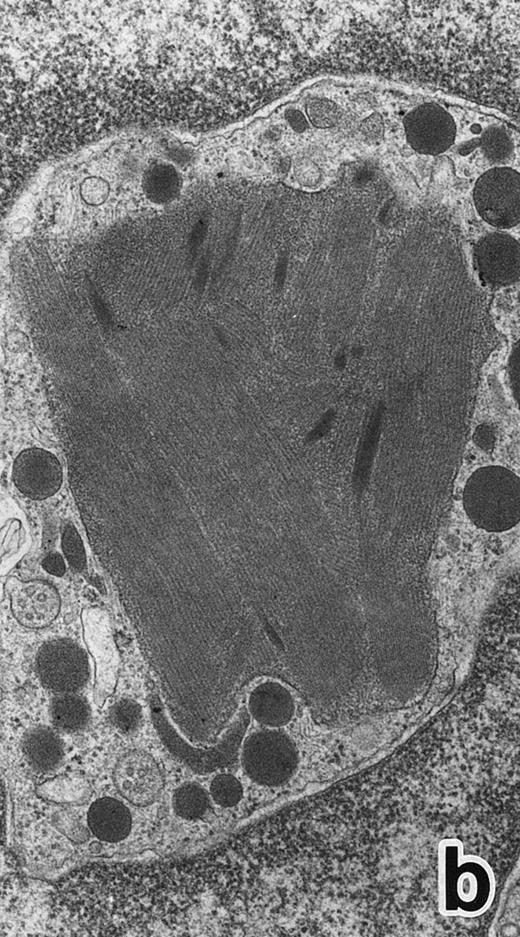

(a) A PMN in patient no. 1 that appeared in the bone marrow after 3 weeks of ATRA treatment. There are numerous granules in the cytoplasm, including spherical, elongated, and even dumbell-shaped granules, all of which are MPO-positive, ie, primary granules. A lipid droplet (L) is also present. (MPO-stained section, original magnification × 15,200.) (b) Higher magnification of a portion of the cytoplasm in (a). MPO-negative secondary granules are not seen. (MPO-stained section, original magnification × 30,900.)

After 2 to 3 weeks of ATRA treatment, maturation of leukemia cells progressed further, and cells resembling normal PMNs appeared (Fig 5). These cells contained multilobulated nuclei with marginally condensed heterochromatin and glycogen particles, characteristic of normal mature neutrophils. rER and free ribosomes became rare as the maturation process proceeded. However, these cells were still rich in primary (type I) granules, which somewhat varied in size and shape, including small and/or elongated forms. A small number of ellipsoid type II primary granules with a nucleoid structure were occasionally observed in patients no. 1 and 2, but not in patient no. 3. Conversely, MPO-positive, small, possibly type III, primary granules were rarely observed intermingled among the larger primary granules in maturing neutrophils in patient no. 3 alone. Despite the ultrastructural features otherwise characteristic of normal mature PMNs, specific granules, which are electron-lucent, elongated or dumbbell-shaped small granules, were not present in the majority of these PMN-like cells, as clearly shown by electron-microscopic cytochemical staining for MPO (Fig 5). The cells contained only MPO-positive primary granules and no MPO-negative secondary granules. A few abnormal primary granules, including Auer rods or C-H type granules, were still present in some cells, and these cells too were consistently devoid of specific granules (Fig 6). Another unusual finding in PMN-like cells at this stage was the presence of large spherical lipid droplets (Fig 5a), which may indicate altered physiological metabolism in these cells,29 because lipid droplets are usually not seen in normal PMNs. Although few in number, PMNs having both primary and secondary granules were also observed (Fig 7), and less mature intermediate forms with indented single nuclei or irregularly lobulated nuclei and numerous primary granules were still present at this stage of ATRA treatment.